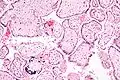

Micrograph of CMV placentitis